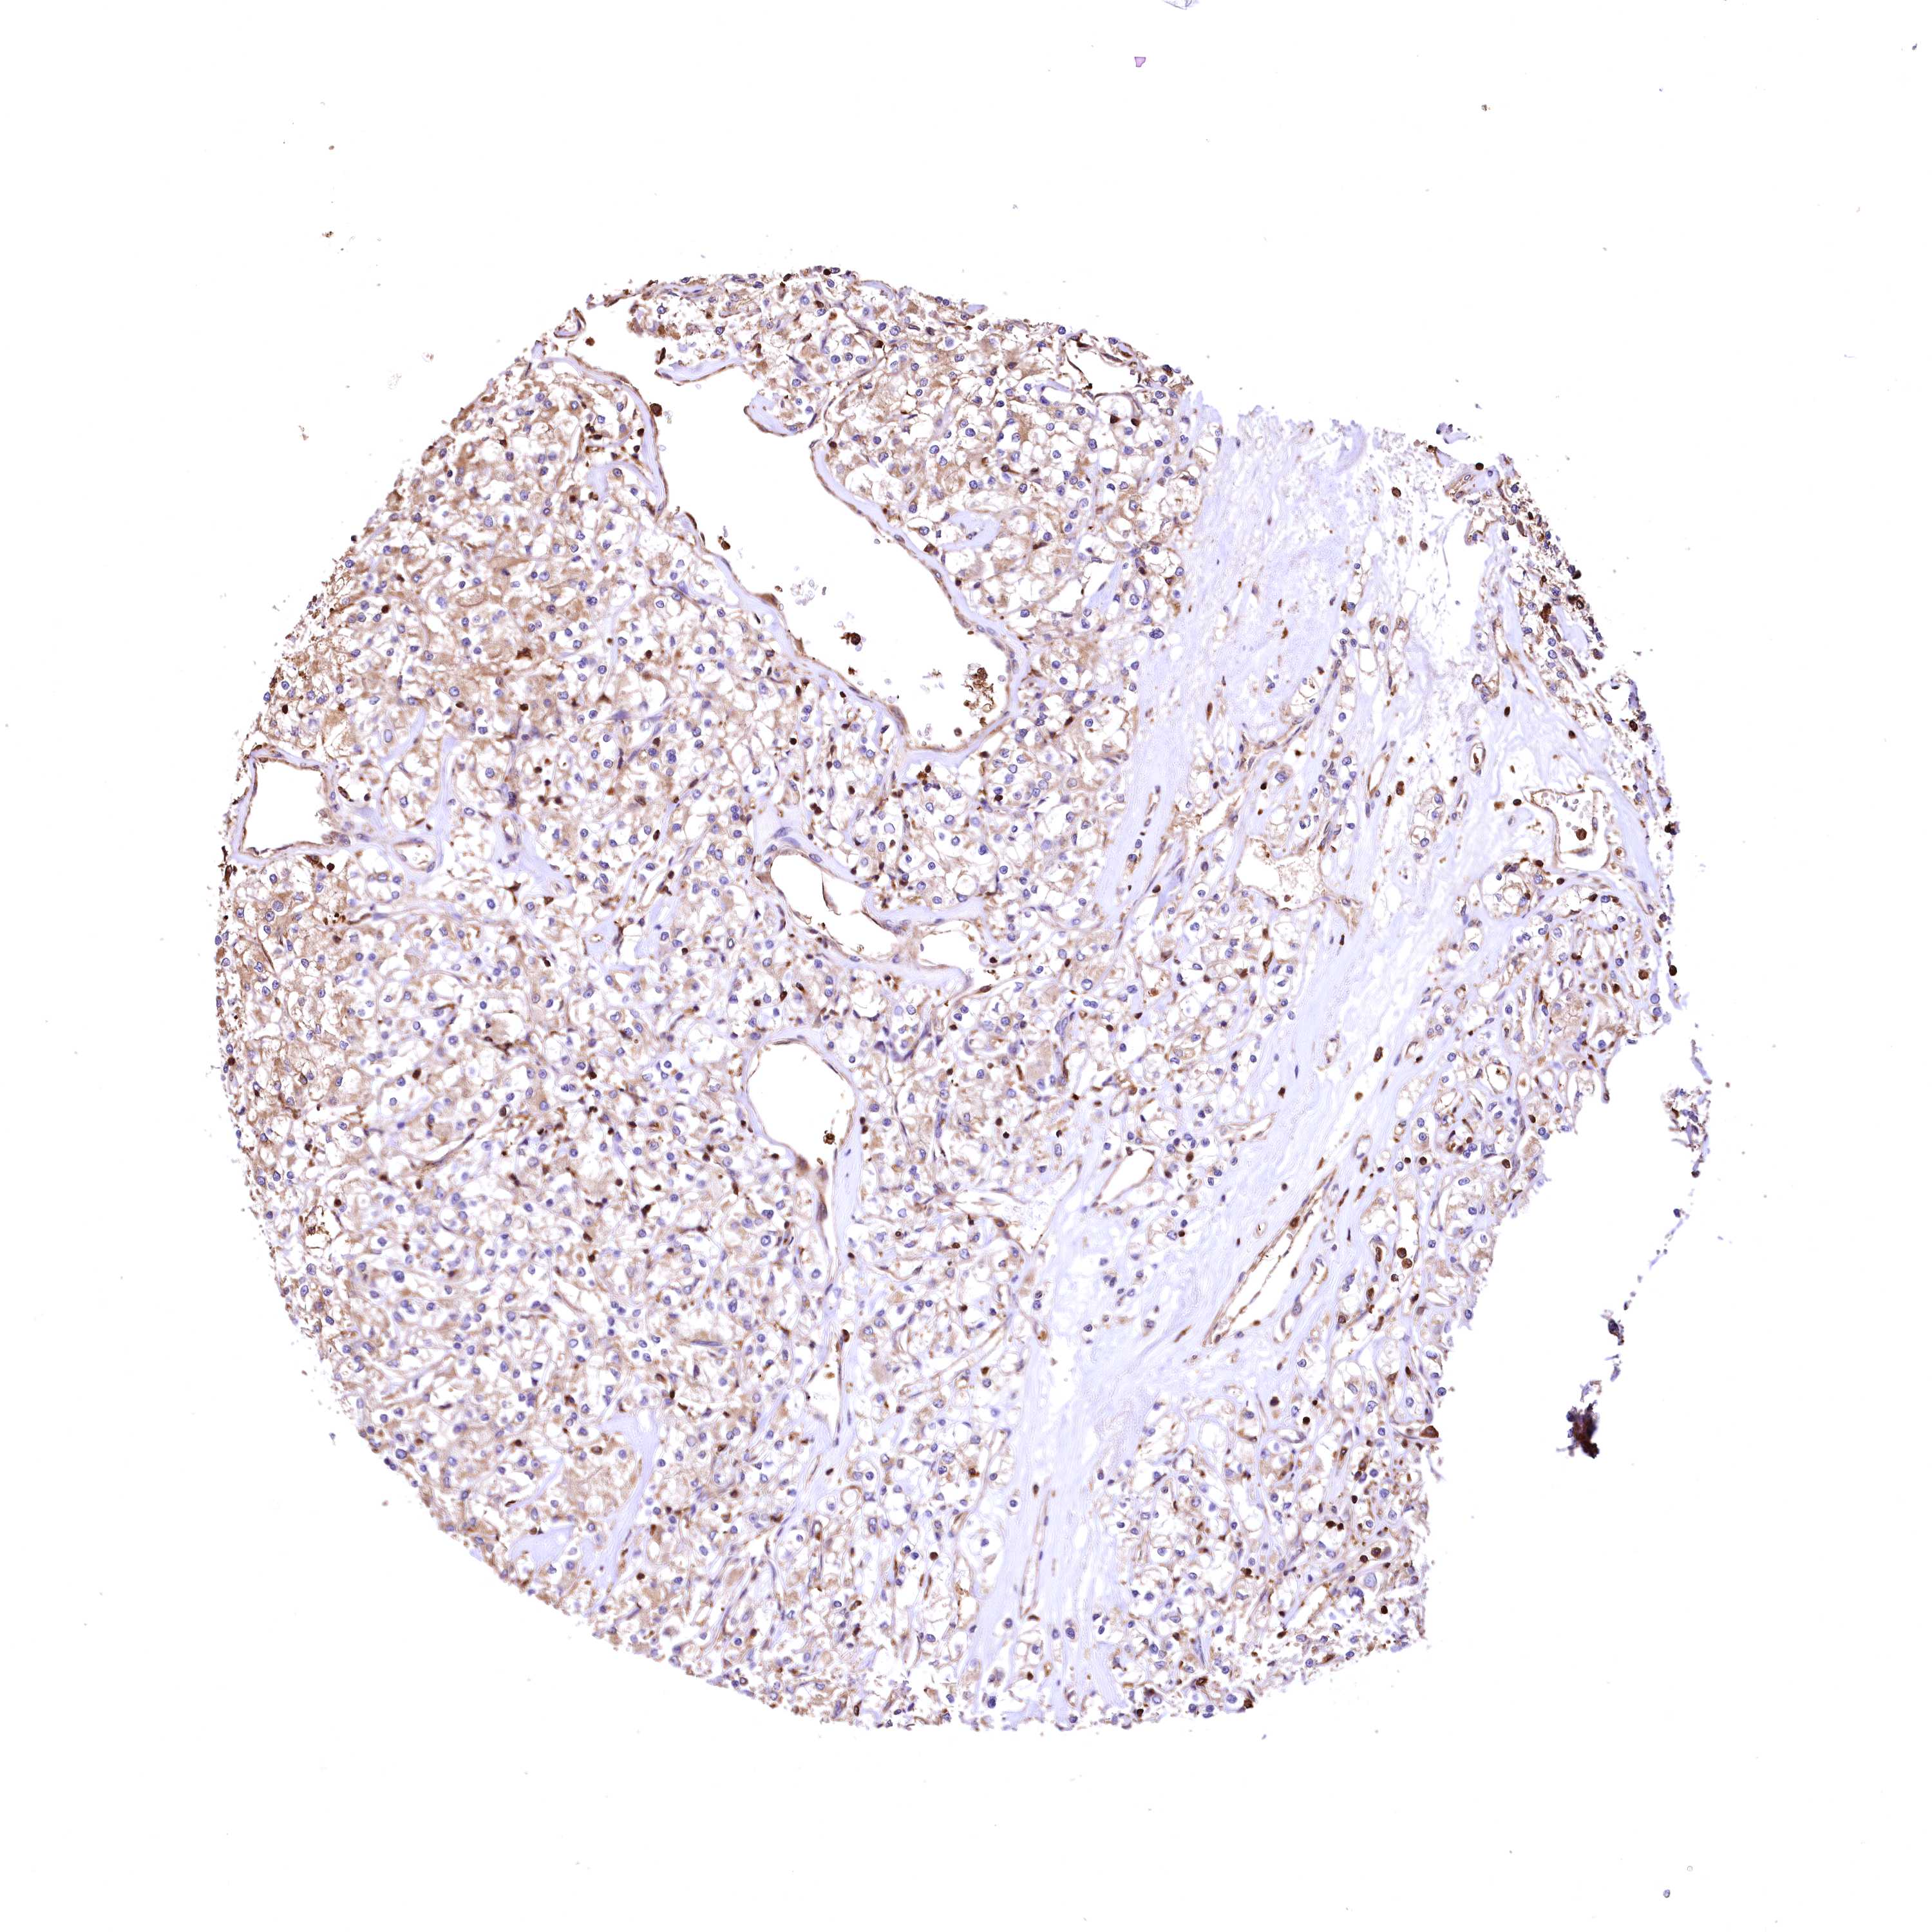

KIDNEY RENAL PAPILLARY CELL CARCINOMA (TCGA) - Interactive survival scatter ploti

The Survival Scatter plot shows the clinical status (i.e. dead or alive) for all individuals in the patient cohort, based on the same data that underlies the corresponding Kaplan-Meier plots. Patients that are alive at last time for follow-up are shown in blue and patients who have died during the study are shown in red.

The x-axis shows the expression levels (FPKM) of the investigated gene in the tumor tissue at the time of diagnosis. The y-axis shows the follow-up time after diagnosis (years). Both axes are complimented with kernel density curves demonstrating the data density over the axes. The top density plot shows the expression levels (FPKM) distribution among dead (red) and alive patients (blue). The right density plot shows the data density of the survived years of dead patients with high and low expression levels respectively, stratified using the cutoff indicated by the vertical dashed line through the Survival Scatter plot. This cutoff is automatically defined based on the FPKM cutoff that minimizes the p-score. The cutoff can be changed by dragging the vertical line or by entering a cutoff value in the square labeled "Current cut-off".

Under the Survival Scatter plot the p-score landscape (black curve; left axis) is shown together with dead median separation (red curve; right axis). Dead median separation is the difference in median mRNA expression between patients who have died with high and low expression, respectively. It is calculated as follows: median FPKM expression of dead patients with high expression - median FPKM expression of dead patients with low expression. This is intended to aid the user in visually exploring custom cutoffs and the associated p-scores and dead median separation.

Individual patient data is displayed and can be filtered by clicking on one or more of the category buttons on the top of the page. Categories describing expression level and patient information include: high, low, alive, dead, female, male and tumor stages. The scale of the x-axis can be toggled between linear and log-scale by clicking on the "x log" button. Mouse-over function shows TCGA ID, patient information and mRNA expression (FPKM) for each patient.

& Survival analysisi

Kaplan-Meier plots summarize results from analysis of correlation between mRNA expression level and patient survival. Patients were divided based on level of expression into one of the two groups "low" (under cut off) or "high" (over cut off). X-axis shows time for survival (years) and y-axis shows the probability of survival, where 1.0 corresponds to 100 percent.

RARS2 is not prognostic in Kidney Renal Papillary Cell Carcinoma (TCGA)

Best expression cut offi

Based on the FPKM value of each gene, patients were classified into two groups and association between prognosis (survival) and gene expression (FPKM) was examined. The best expression cut-off refers the FPKM value that yields maximal difference with regard to survival between the two groups at the lowest log-rank P-value. Best expression cut-off was selected based on survival analysis .